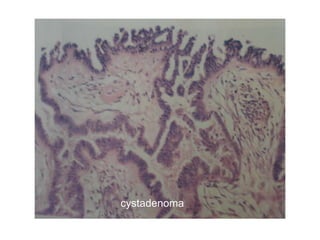

Cystadenoma

• Benign epithelial tumours forming large cystic masses as in the

ovary.

Papillary cystadenoma